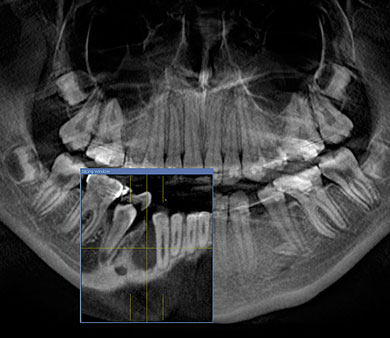

Gefahr der Nervverletzung bei der Weisheitszahnentfernung

Die Gefahr von Nervverletzungen können wir dadurch erheblich reduzieren!

Lagebestimmung von verlagerten Zähnen

Im normalen Röntgenbild kann die genaue Lage nicht sicher festgestellt werden.

In unserem Fall hier lag ein Zahn zur Lippe hin (*) und ein Zahn im Gaumen (**). Mit diesen Informationen können wir minimalinvasiv und sehr schonend operieren!